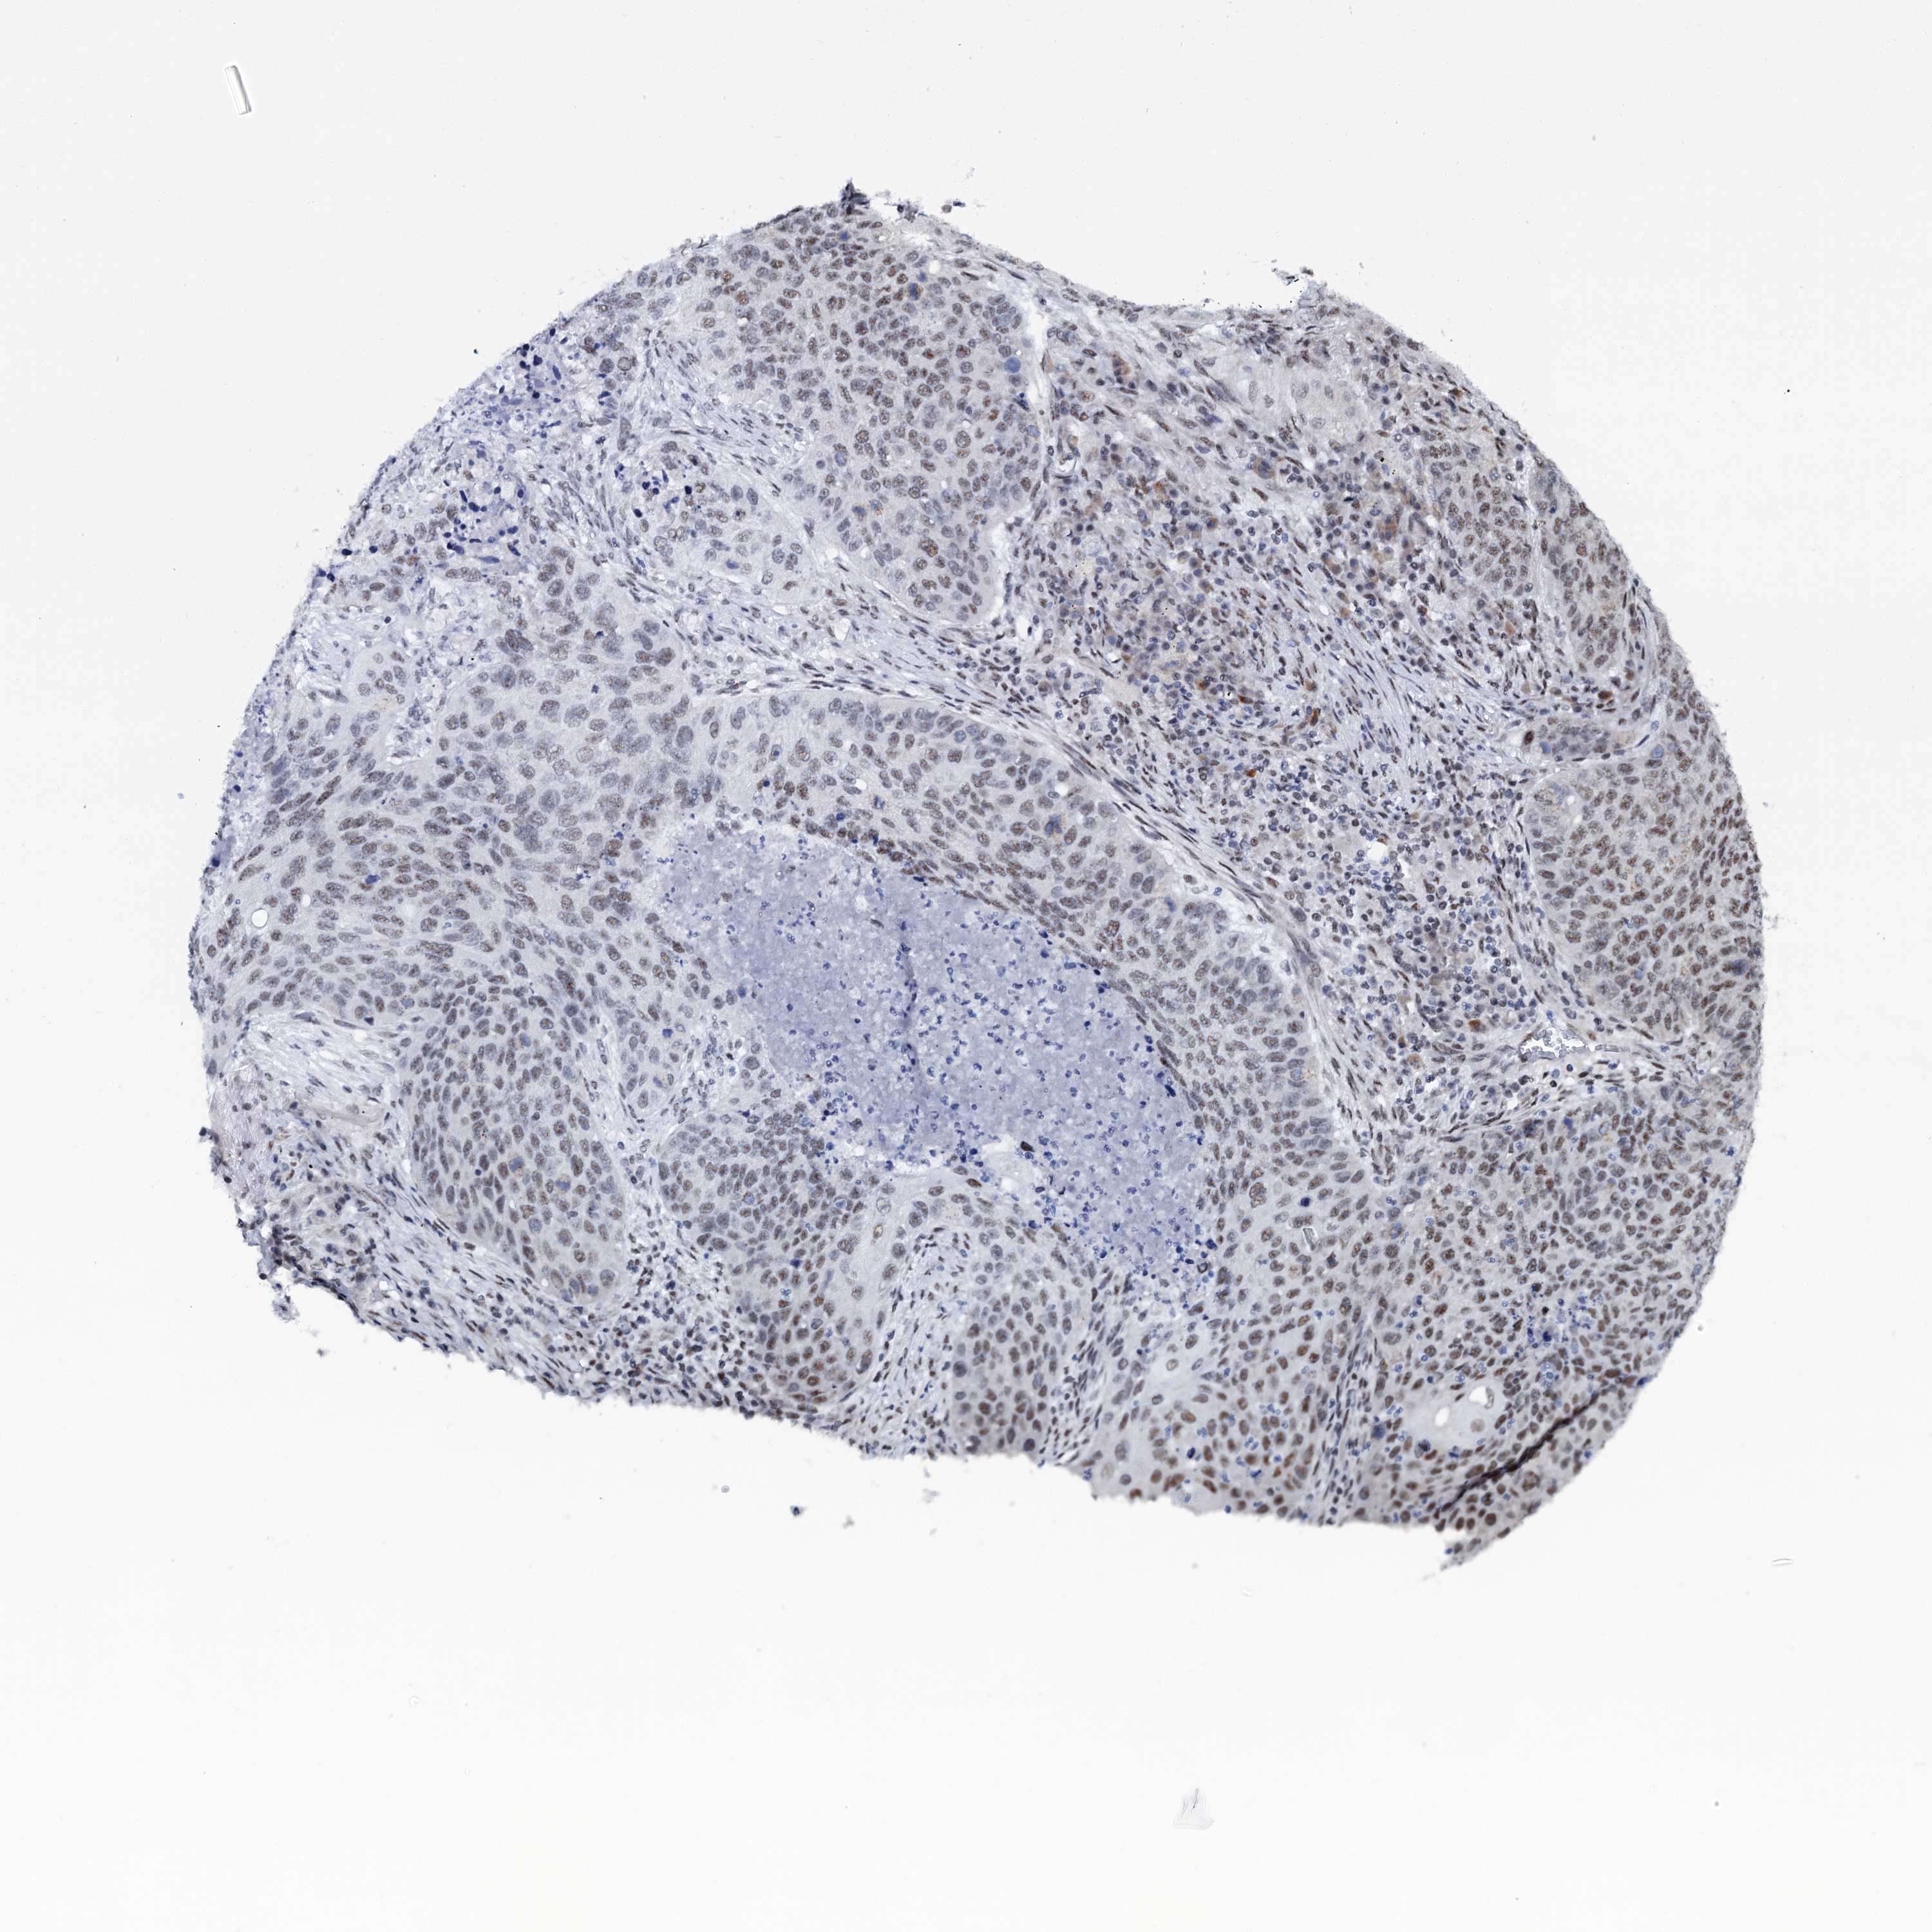

LUNG SQUAMOUS CELL CARCINOMA (TCGA) - Interactive survival scatter ploti

The Survival Scatter plot shows the clinical status (i.e. dead or alive) for all individuals in the patient cohort, based on the same data that underlies the corresponding Kaplan-Meier plots. Patients that are alive at last time for follow-up are shown in blue and patients who have died during the study are shown in red.

The x-axis shows the expression levels (FPKM) of the investigated gene in the tumor tissue at the time of diagnosis. The y-axis shows the follow-up time after diagnosis (years). Both axes are complimented with kernel density curves demonstrating the data density over the axes. The top density plot shows the expression levels (FPKM) distribution among dead (red) and alive patients (blue). The right density plot shows the data density of the survived years of dead patients with high and low expression levels respectively, stratified using the cutoff indicated by the vertical dashed line through the Survival Scatter plot. This cutoff is automatically defined based on the FPKM cutoff that minimizes the p-score. The cutoff can be changed by dragging the vertical line or by entering a cutoff value in the square labeled "Current cut-off".

Under the Survival Scatter plot the p-score landscape (black curve; left axis) is shown together with dead median separation (red curve; right axis). Dead median separation is the difference in median mRNA expression between patients who have died with high and low expression, respectively. It is calculated as follows: median FPKM expression of dead patients with high expression - median FPKM expression of dead patients with low expression. This is intended to aid the user in visually exploring custom cutoffs and the associated p-scores and dead median separation.

Individual patient data is displayed and can be filtered by clicking on one or more of the category buttons on the top of the page. Categories describing expression level and patient information include: high, low, alive, dead, female, male and tumor stages. The scale of the x-axis can be toggled between linear and log-scale by clicking on the "x log" button. Mouse-over function shows TCGA ID, patient information and mRNA expression (FPKM) for each patient.

& Survival analysisi

Kaplan-Meier plots summarize results from analysis of correlation between mRNA expression level and patient survival. Patients were divided based on level of expression into one of the two groups "low" (under cut off) or "high" (over cut off). X-axis shows time for survival (years) and y-axis shows the probability of survival, where 1.0 corresponds to 100 percent.

SREK1 is not prognostic in Lung Squamous Cell Carcinoma (TCGA)

Best expression cut offi

Based on the FPKM value of each gene, patients were classified into two groups and association between prognosis (survival) and gene expression (FPKM) was examined. The best expression cut-off refers the FPKM value that yields maximal difference with regard to survival between the two groups at the lowest log-rank P-value. Best expression cut-off was selected based on survival analysis .

When clicking on this number, the vertical dashed line indicating cut-off, the interactive survival plot, and the Kaplan-Meier curve will be adjusted to show results based on the best expression cut-off.

: 1.64

Median expressioni

Median expression refers to the median FPKM value calculated based on the gene expression (FPKM) data from all patients in this dataset. When clicking on this number, the vertical dashed line indicating cut-off, the interactive survival plot, and the Kaplan-Meier curve will be adjusted to show results based on the median expression.

: N/A

P scorei

Log-rank P value for Kaplan-Meier plot showing results from analysis of correlation between mRNA expression level and patient survival.

N/A

5-year survival highi

5-year survival for patients with higher expression than the expression cutoff.

For melanoma and glioma, 3-year survival is shown.

5-year survival lowi

5-year survival for patients with lower expression than the expression cutoff.

Average pTPM 2.3

Number of samples 489